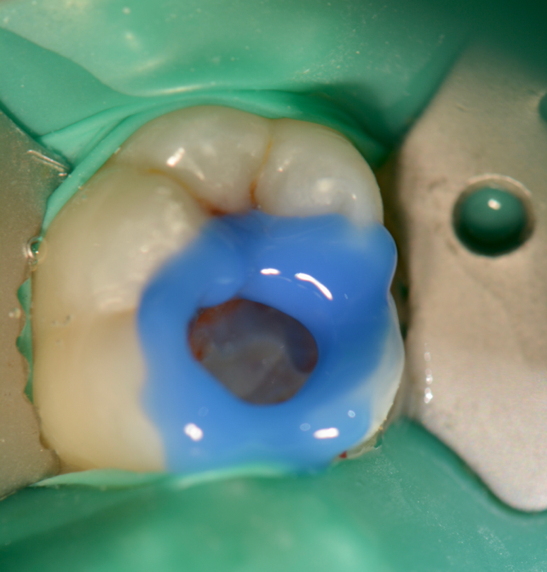

Fig .5. Selective etching

Next, selective etching protocol with phosphoric acid was performed for 20seconds (Fig. 5). Then the preparation was rinsed and gently air-dried. Dentin adhesive (Universal Adhesive, Parkell) was applied that may be used with self-etch, selective-etch (ie, etching only the enamel), and total-etch methods. The adhesive was applied to the preparation using a rubbing motion for 20 seconds keeping the surface moist (Fig 6). A second coat of the adhesive was applied for an additional 20 seconds. Using an air-water syringe, the surface was air-thinned for 10 to 15 seconds to evaporate the solvent. The surfaces were light-cured for 20 seconds.